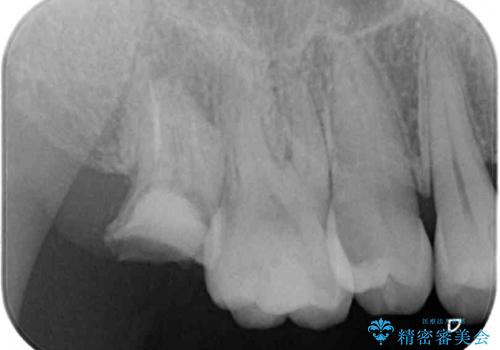

- 長年放置しているむし歯を気にして来院された患者様です。

外側を向いている上顎の奥歯は歯ブラシが十分に届かないため、むし歯となるケースが多いのですが、今回むし歯となってしまった歯がそれで、ボロボロになって根だけが残っている状態でした。

患者様と相談し、抜歯をした上でインプラントによる補綴治療を行うこととしました。